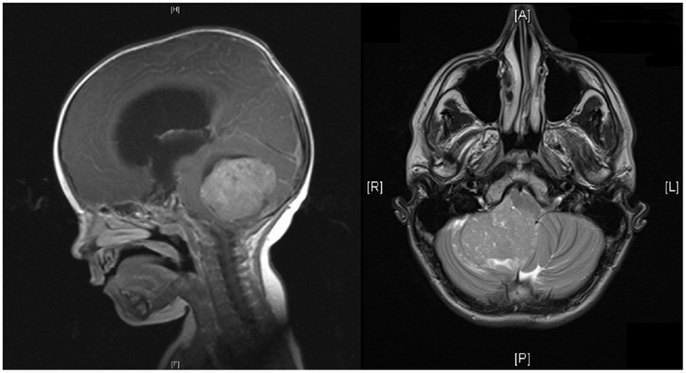

۲. آزمایشهای تصویربرداری: تصویربرداری رزونانس مغناطیسی (MRI) و اسکن توموگرافی کامپیوتری (CT) برای ایجاد تصاویر دقیق از مغز و مکانیابی هرگونه تومور استفاده میشوند.